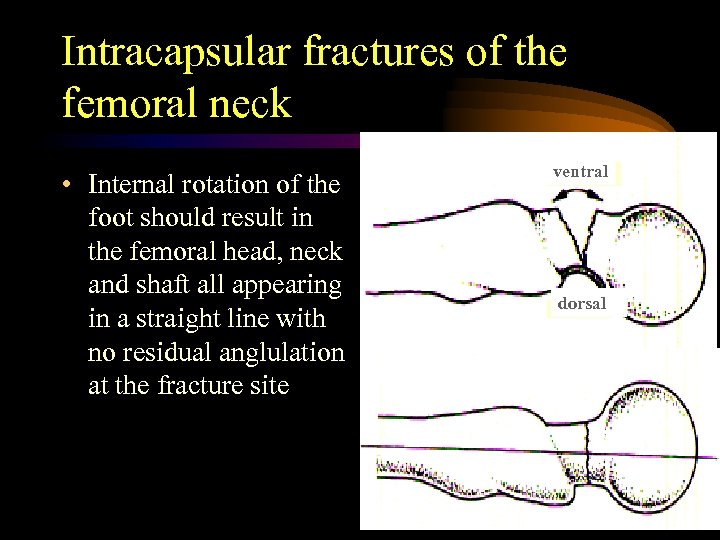

Intracapsular fractures of the femoral neck • Internal rotation of the foot should result in the femoral head, neck and shaft all appearing in a straight line with no residual anglulation at the fracture site ventral dorsal

Intracapsular fractures of the femoral neck • Internal rotation of the foot should result in the femoral head, neck and shaft all appearing in a straight line with no residual anglulation at the fracture site ventral dorsal